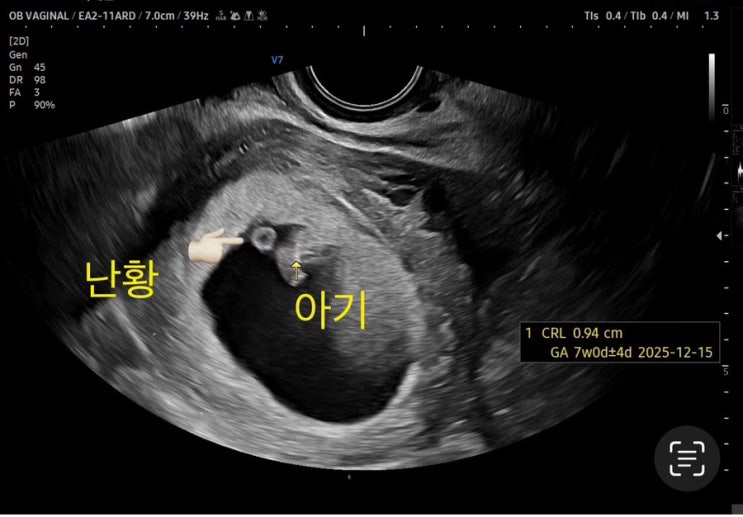

생리일로 봤을땐 12월14일이였고 5주 아기집크기로는 12월12일 7주 검진때 12월15일 9주검진때 12월17일 출...

두번째이야기) 7주 초음파 보고온 날

나는 동탄 제일병원으로 진료를 다니고 있고 첫째 하원시간이 빨라서 오전밖에 진료를 볼 수가 없는 상황인...